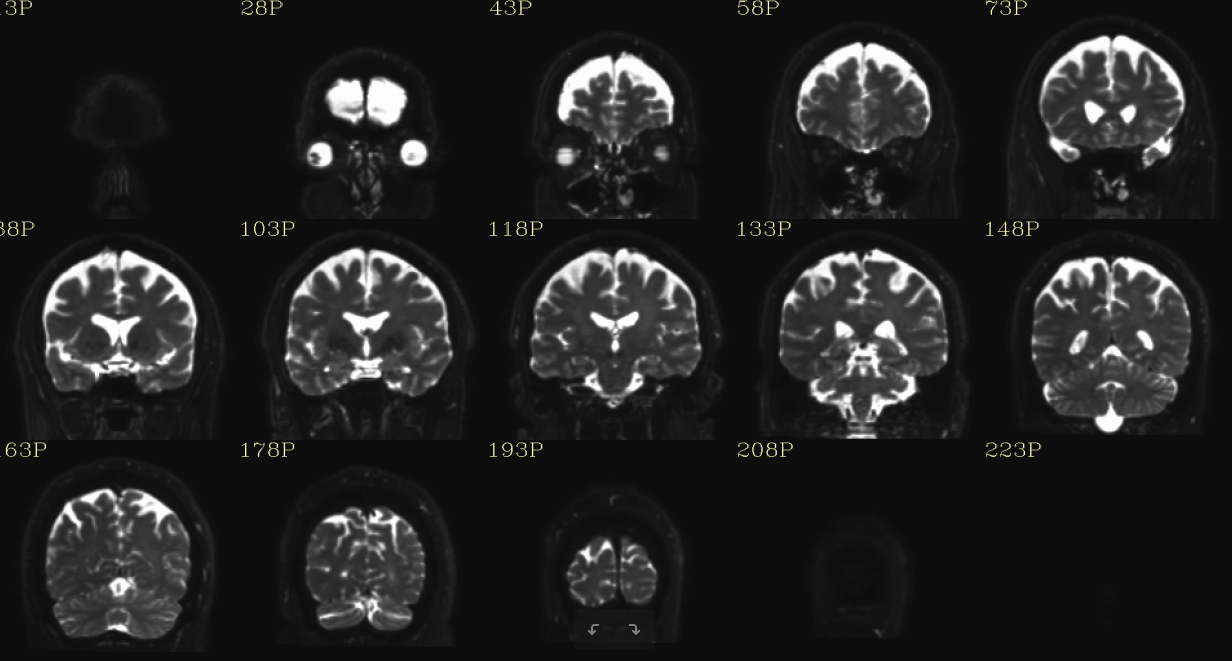

Coronal

8.2. RAW STRUCTURAL USED QC

Note: There are gif files also saved for the raw DWI and processed DWI files. These are animated gif files that will play when you open them using any image file viewer. When you play the gif files for before (without DMC in name) and after correction (with DMC in name), you will be able to appreciate the eddy and motion distortion correction performed. Please use this information to understand if the correction has worked effectively on your data. Also, if you notice interleave slice motion within a volume (example shown in the section 11 Quality assessment, please use the suggested steps of remediation. The structural quality check is of importance, as all of the corrections in DIFFPREP and DRBUDDI rely on the information from the structural. If you notice that the final images are not effectively corrected, it is helpful to have a qc of the structural data used to assess if the reference data is optimal quality. A reference data with motion or excessive soft tissue included can introduce artifacts in the corrections performed in DIFFPREP/DRBUDDI processing.